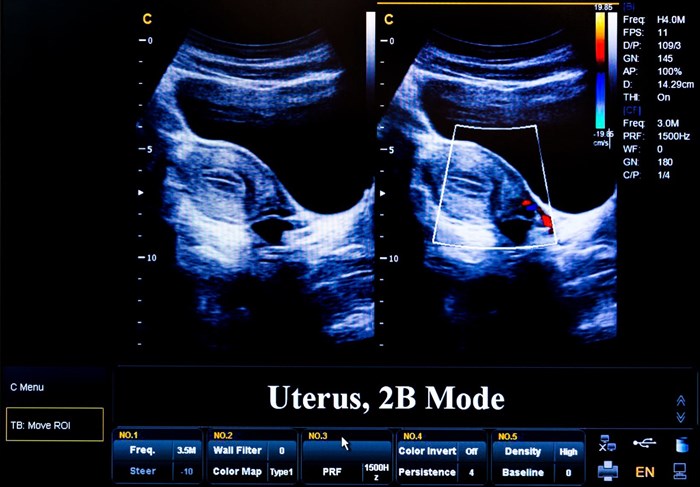

• Two-dimensional ultrasound images (2D ultrasound): This is the most common type of visual image used. A 2D image uses a series of flat, two-dimensional cross section visuals of the area of the body being scanned. This type of image is used for most obstetric and diagnostic evaluations.

Two-dimensional (2-D) ultrasound scan example.